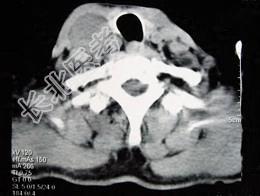

- 多项选择题男性,70岁, 右侧颈部无痛性肿块3个月,CT扫描如图所示, 请选择正确的描述和答案 ( )

A、右颈动脉间隙内见类圆形软组织肿块影,密度欠均匀,边缘光整

B、右侧颈静脉被推压至肿块外后方

C、右侧颈动脉被推压至肿块内后方

D、考虑迷走神经源性肿瘤

E、考虑交感神经源性肿瘤